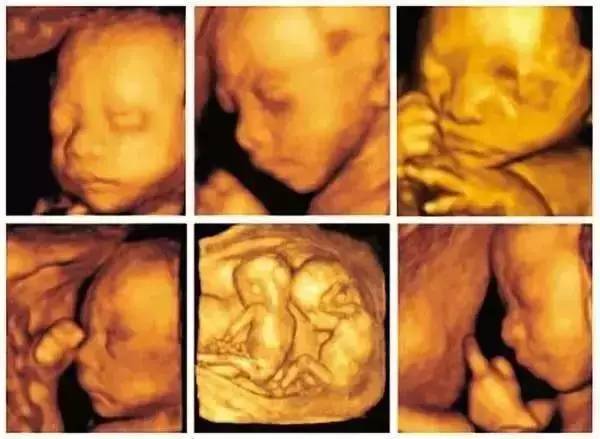

通過四維彩超技術,我們可以清晰地觀察到睪丸的內部結構,在四維彩超圖像上,睪丸通常呈現為一種均勻的回聲結構,其中可以看到細小的血管、淋巴管和神經,還可以觀察到睪丸內的睪丸實質和附睪等結構,這些結構的清晰可見有助于醫(yī)生進行準確的診斷。